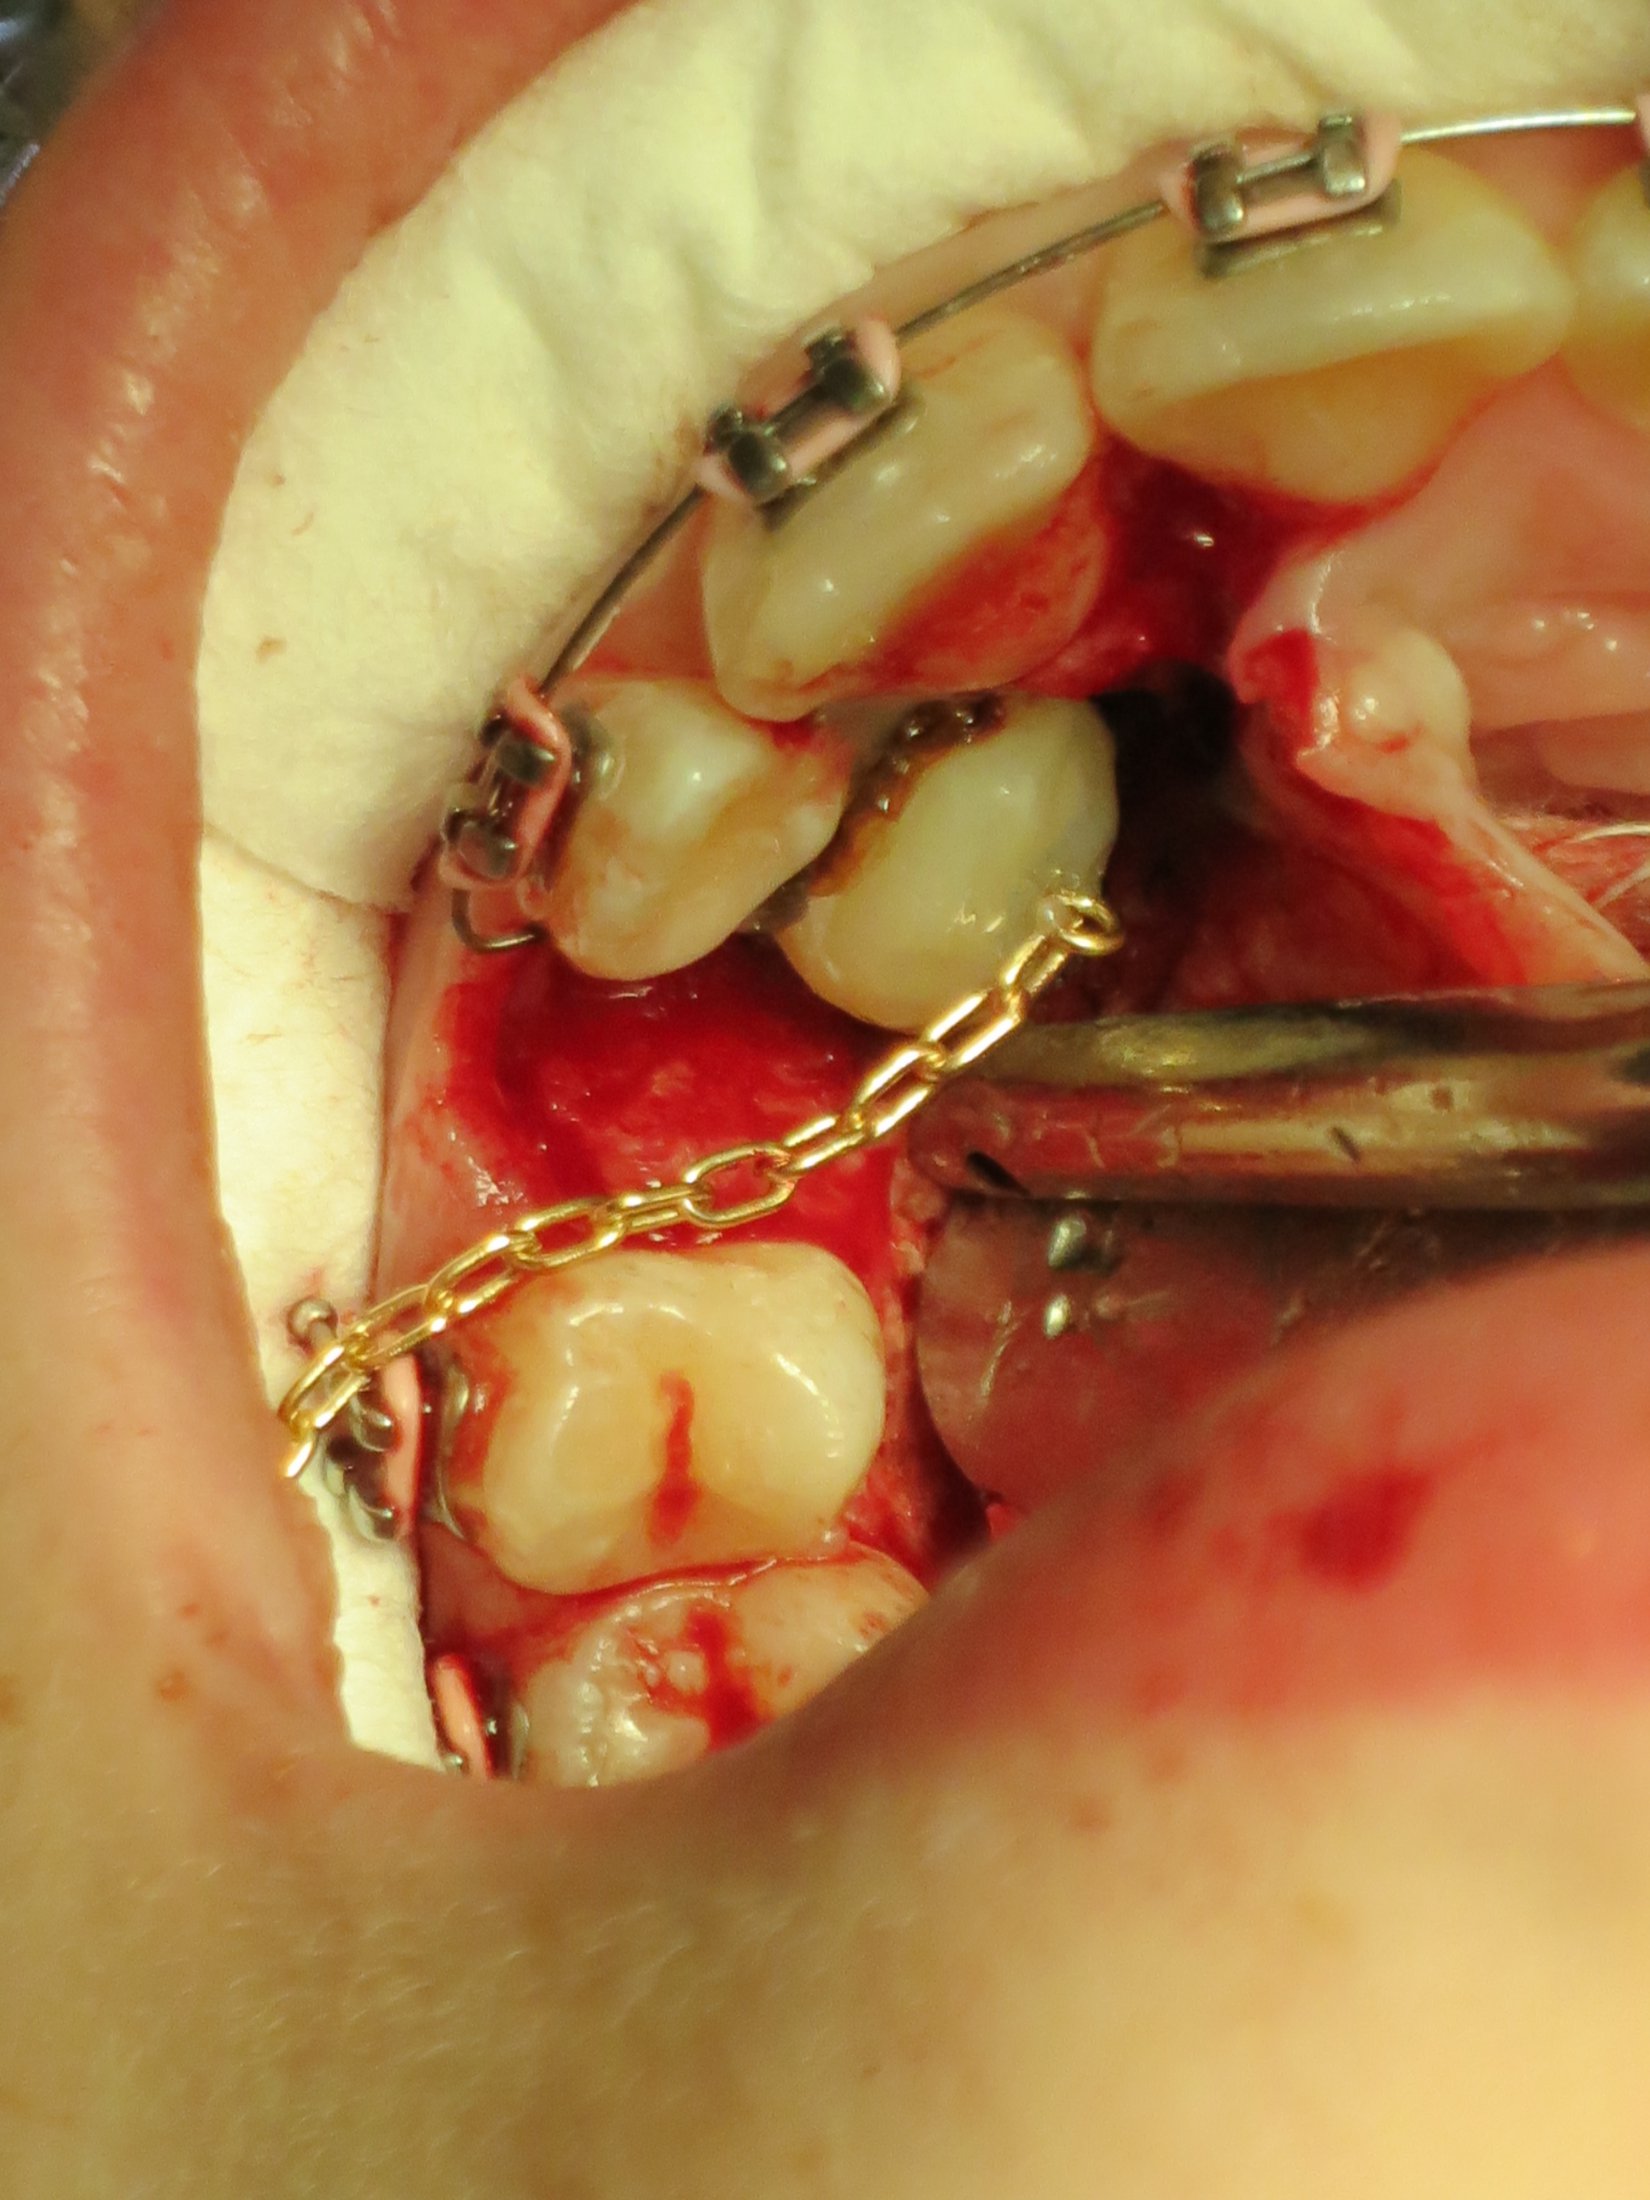

Bracket and chain an orthodontic bracket is glued to the tooth. Sometimes the gold chain may dangle down. Typically, newsmile needs a preliminary consultation, which is normally totally free of charge.

How do they pull down teeth with braces? Orthodontic chains for pulling teeth down. Over time the dentist would tighten then chain.

I had chains on m teeth to pull them down as well. It can be used to close space after a tooth is extracted, or used for generalized spacing. It is a long process because it had to come down slow so they don't pull the permanent teeth out.